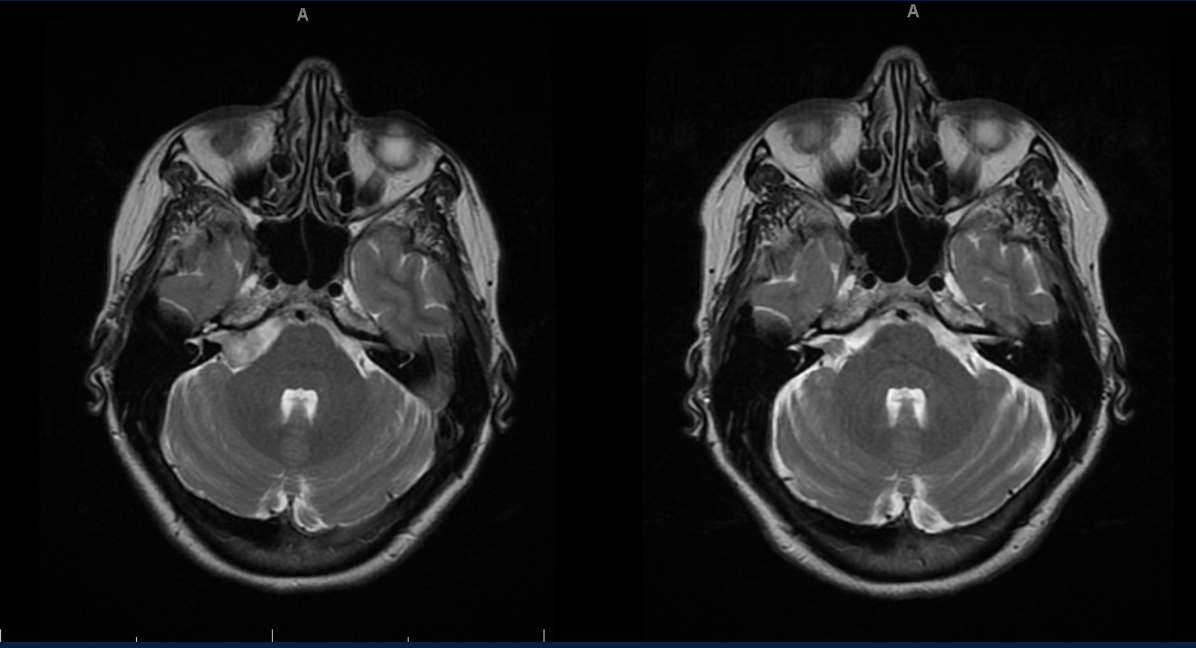

Results

Five participants with NMDAr-AIE (4F/1M, mean age 30, SD 7) and four HC (3F/1M, mean age 36, SD 6) were included. All NMDAr-AIE participants had normal or non-specific T2 hyperintensities on initial imaging and had received immunotherapy. The mean Modified Rankin Score (MRS) on discharge was 2. MWF (mean ± SD) for normal-appearing white matter, corpus callosum, corticospinal tract, and superior longitudinal fasciculus were 0.10±0.02, 0.12±0.02, 0.15±0.03, 0.12±0.02, which were very similar to HC at 0.09±0.02, 0.11±0.01, 0.15±0.02, and 0.11±0.02, respectively.

Fig. 1 Myelin Water Imaging of two selected patients

Screenshot 2025 06 01 at 12.05.23 pm

Conclusions and Future Direction

Myelin Water Imaging showed no myelin pathology in five NMDAr-AIE patients, with MWF and MHI values comparable to HC, suggesting that myelin pathways are relatively preserved post-recovery from AIE. Moving forward, we aim to continue recruiting healthy controls, patients post-recovery and those experiencing active disease to determine if there are any MWF abnormalities throughout the disease course. Future studies are needed to assess MWF changes in other antibody-mediated encephalitides.